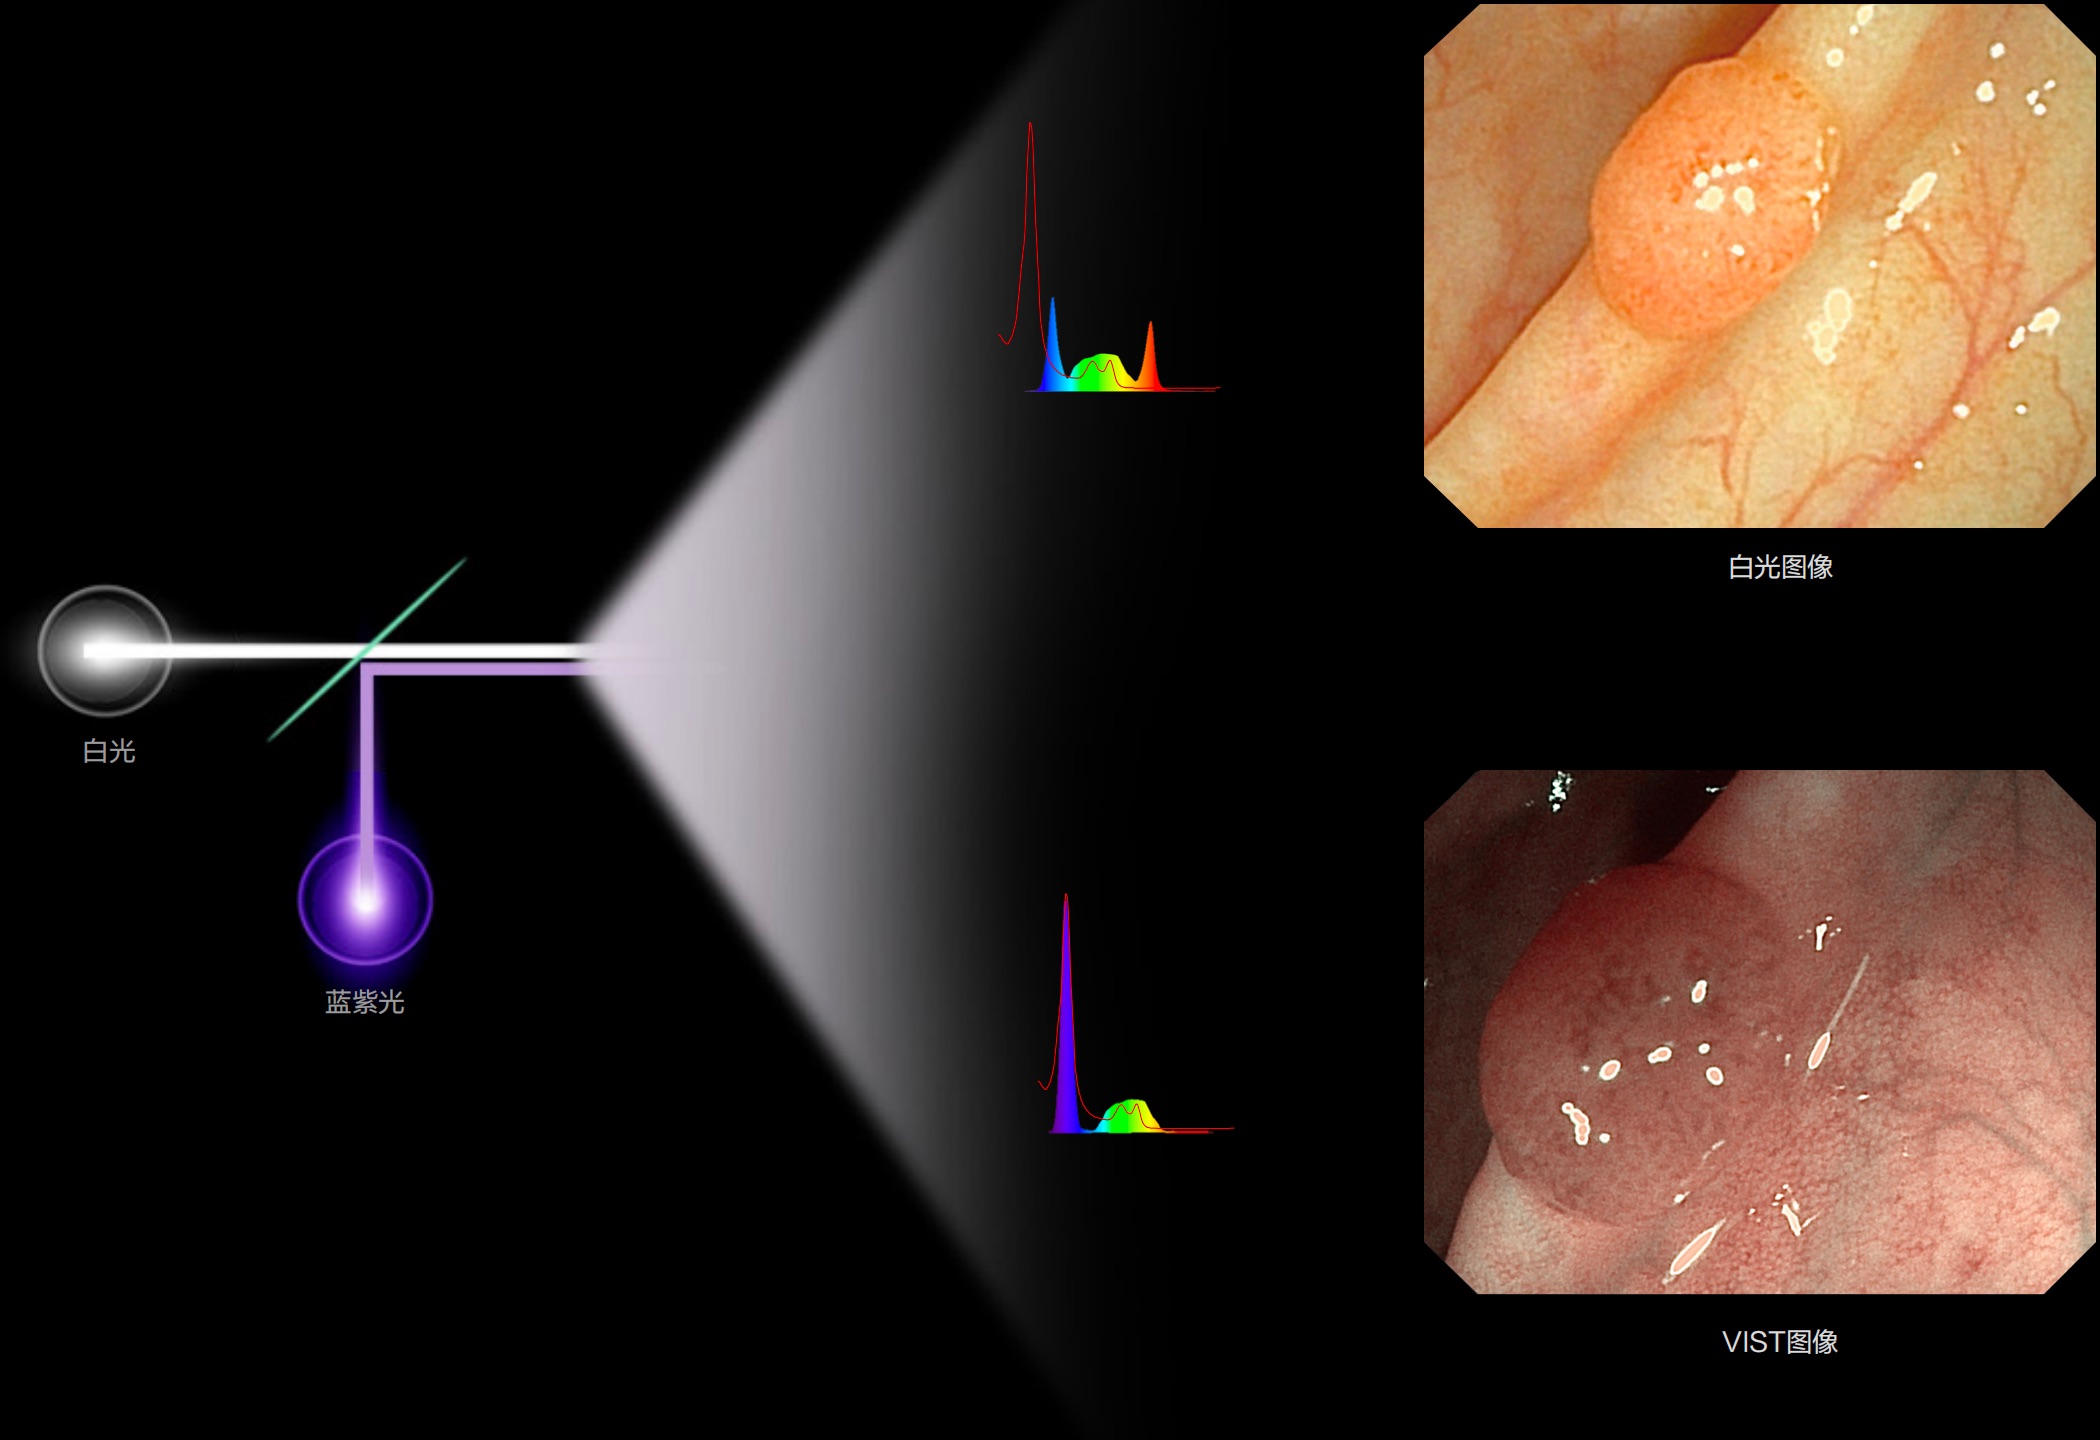

光电复合染色成像

(Versatile Intelligent Staining Technology)

能够凸显黏膜浅层血管轮廓和黏膜表面微结构,适用于中、近景观察下的早癌精确诊断。